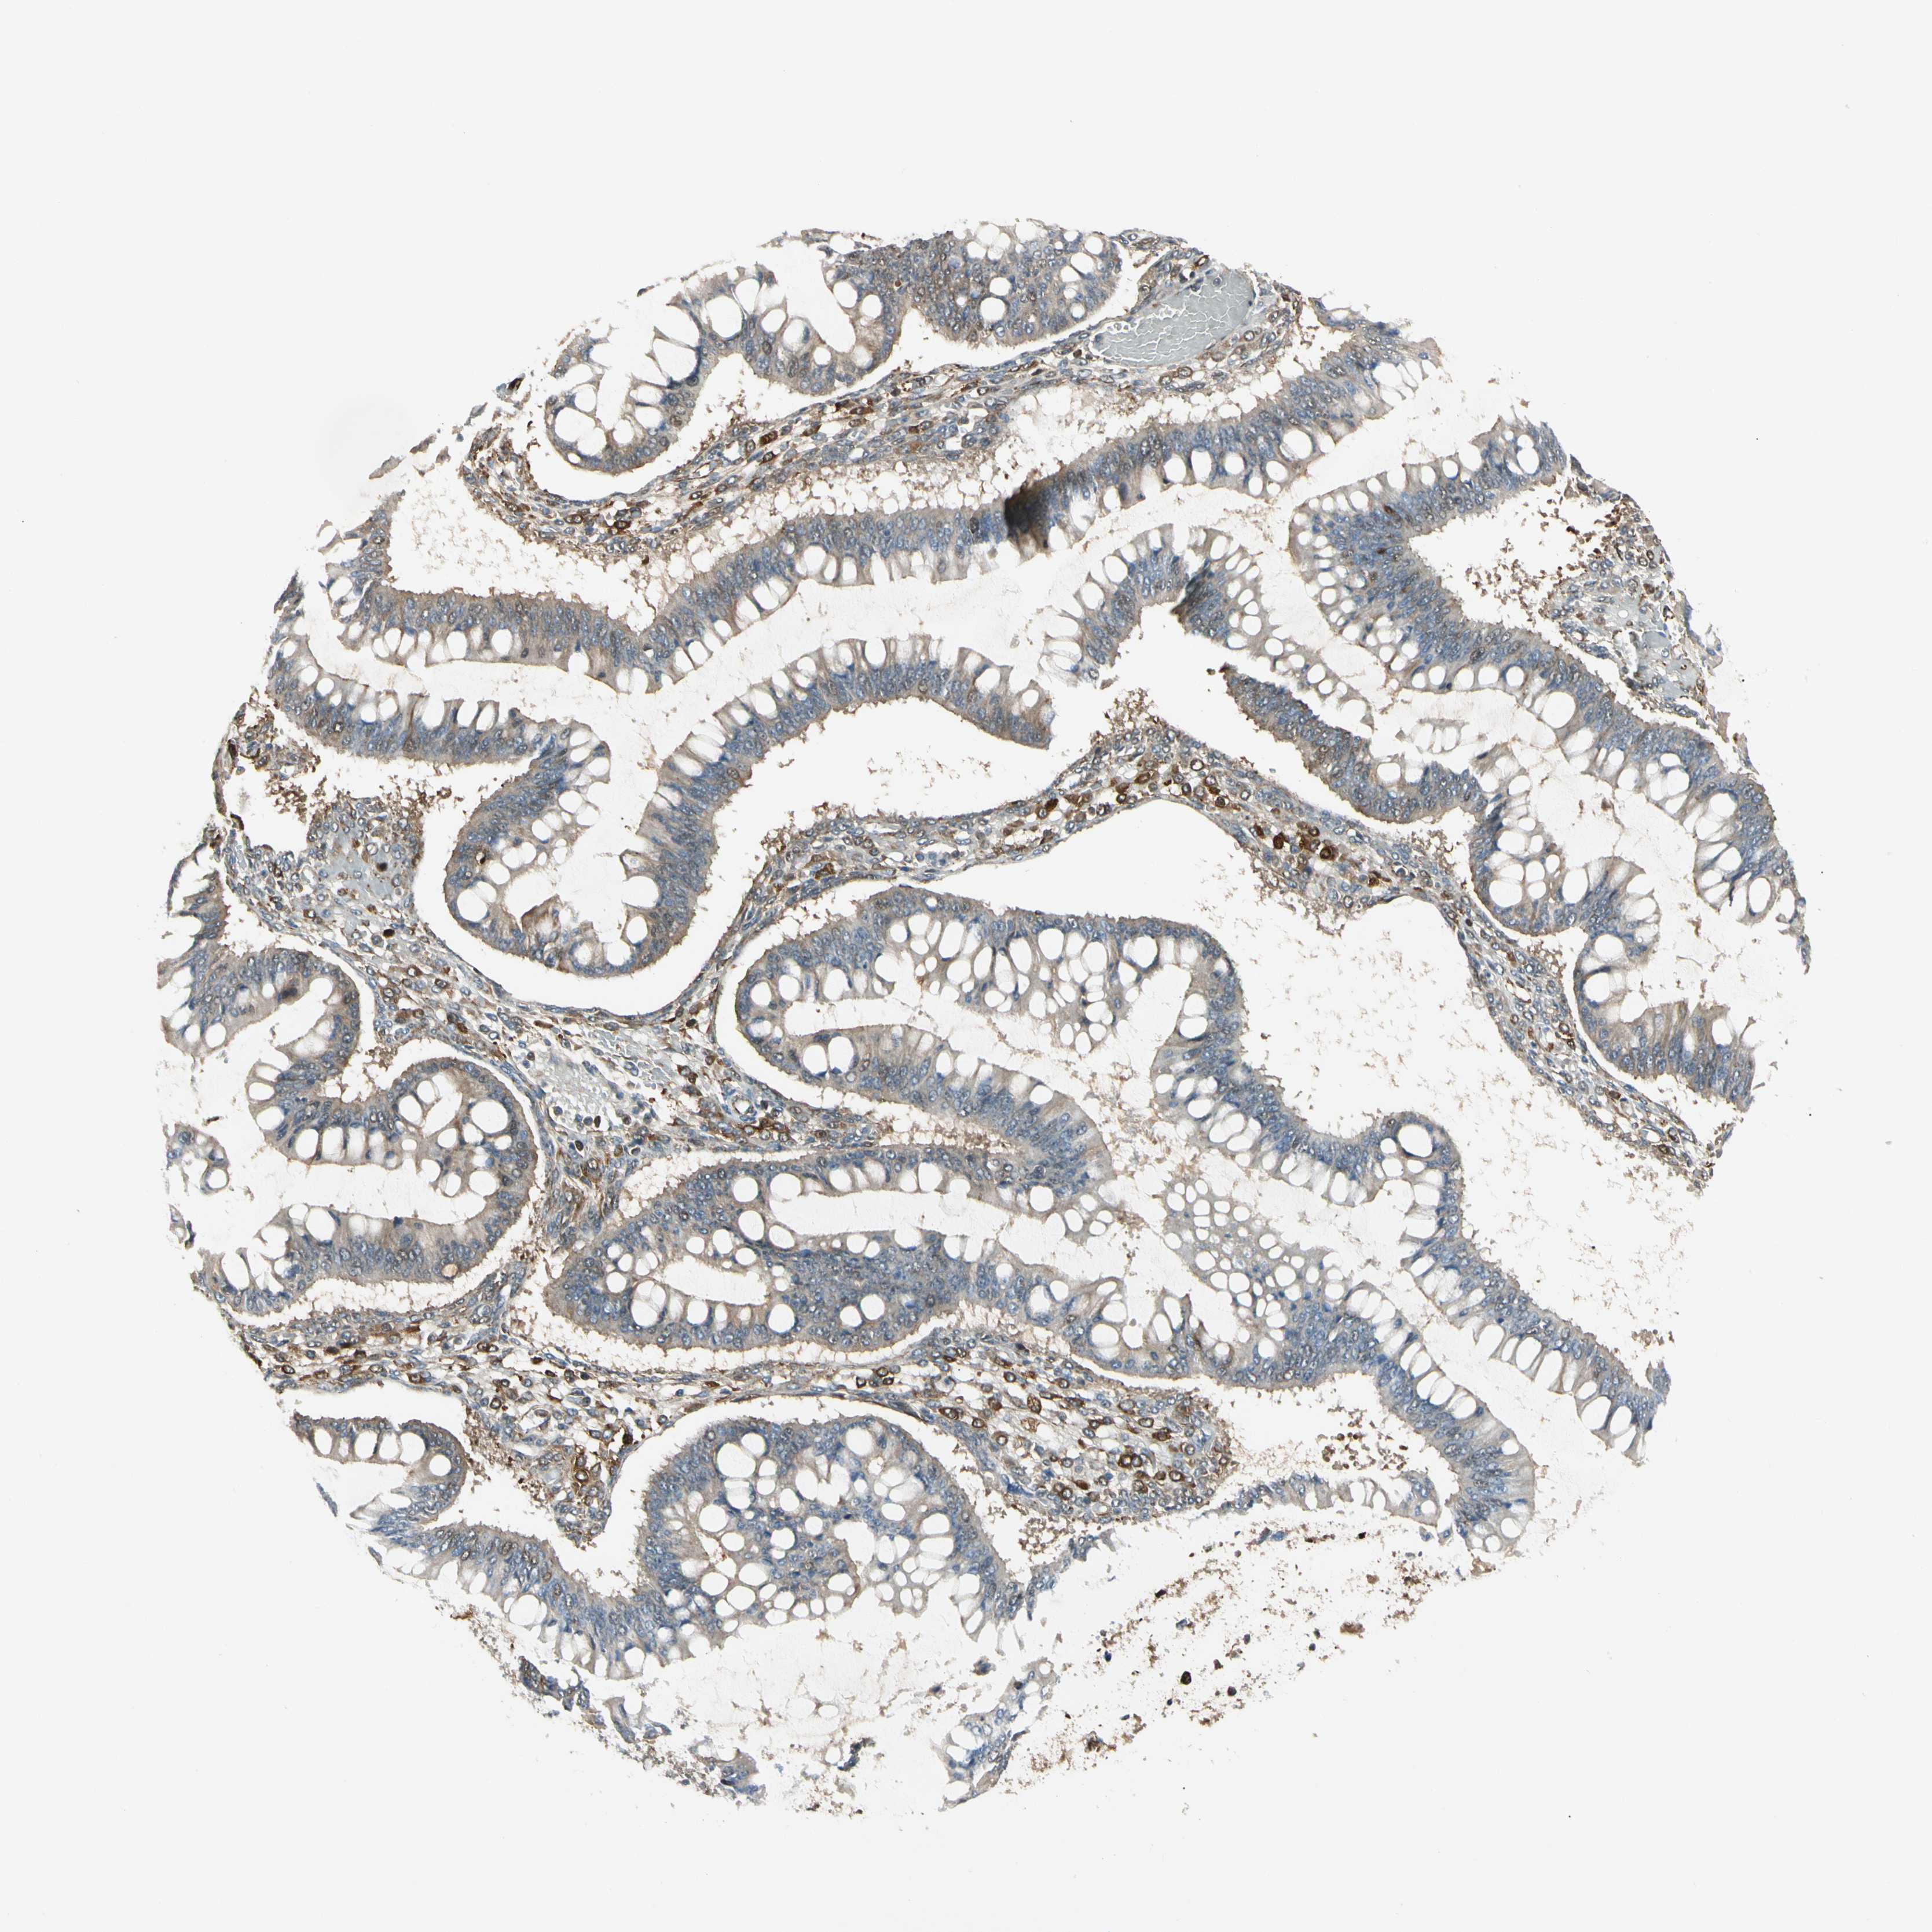

OVARIAN CANCER - Protein expressioni

A mouse-over function shows sample information and annotation data. Click on an image to view it in a full screen mode. Samples can be filtered based on level of antibody staining by selecting one or several of the following categories: high, medium, low and not detected. The assay and annotation is described here.

Note that samples used for immunohistochemistry by the Human Protein Atlas do not correspond to samples in the TCGA dataset.

Antibody stainingi

Antibody staining in the annotated cell types in the current human tissue is reported as not detected, low, medium, or high, based on conventional immunohistochemistry profiling in selected tissues. This score is based on the combination of the staining intensity and fraction of stained cells.

Each image is clickable and will lead to virtual microscopy that enables deeper exploration of all samples and also displays staining intensity scores, fraction scores and subcellular localization as well as patient and tissue information for each sample.

Antibody CAB008623

Staining

High

Medium

Low

Not detected

Intensity

Strong

Moderate

Weak

Negative

Quantity

>75%

75%-25%

<25%

None

Location

Nuclear

Cytoplasmic/membranous

Cytoplasmic/membranous,nuclear

Cystadenocarcinoma, serous, NOS

Carcinoma, endometroid

Cystadenocarcinoma, mucinous, NOS

Carcinoma, NOS